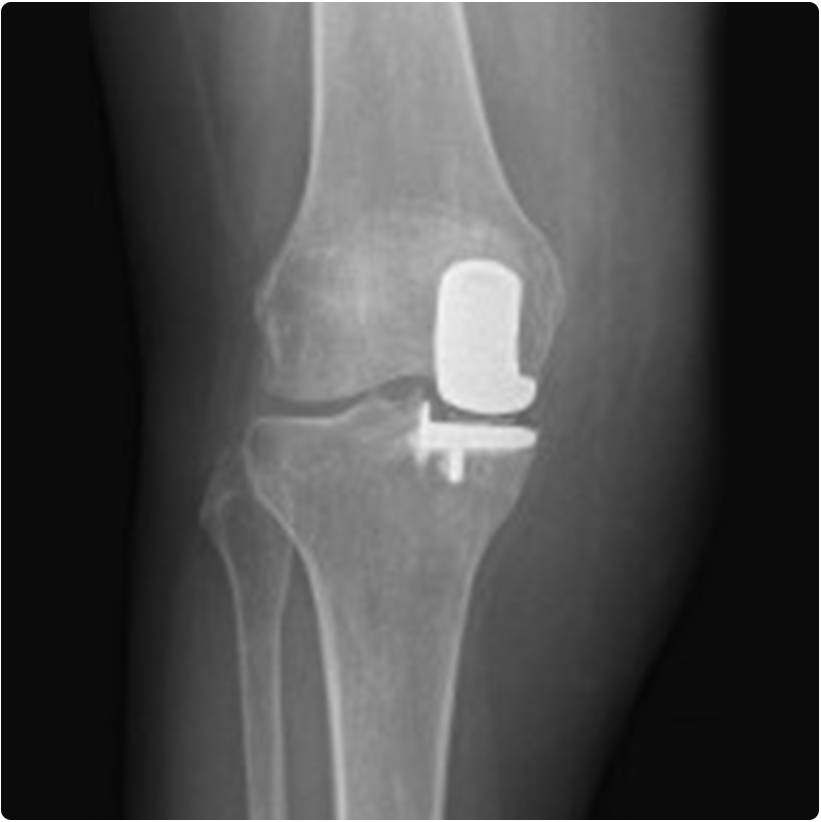

Dizin tamamına ilerlememiş, belli bir bölgesini yaygın olarak tutmuş osteoartritte tam diz protezine alternative olarak kısmi (yarım) diz protezi yapılabilmektedir. Bu ameliyat daha küçük bir kesiden yapılan, hem dizin bozulan eksenini düzelten, hem de aşınmış kıkırdak bölgesine konan protezle sorunu ortadan kaldıran bir işlemdir. Ameliyat için doktorunuzun muayene ve incelemeleriyle karar vereceği bazı ön şartlar vardır. Bu şartlara uygun olan hastalarda titiz uygulama ile çok iyi sonuçlar alınabilmektedir.

Kısmi diz protezinin avantajları; küçük bir kesiden yapılması, dizin sadece aşınmanın olduğu bölgesine uygulanması ve sağlam kıkırdak bölgelerinin korunmuş olması, enfeksiyon olasılığının çok düşük olması, hastanın ameliyattan sonra günlük aktivitelere uyumunun kısa sure içinde gerçekleşmesi, hastanede daha kısa kalış süresidir. Uygun hastalara, titiz bir cerrahi teknik ile uygulandığında çok uzun süreli (20 yıldan fazla) çok iyi sonuçlar elde edilebilmektedir.